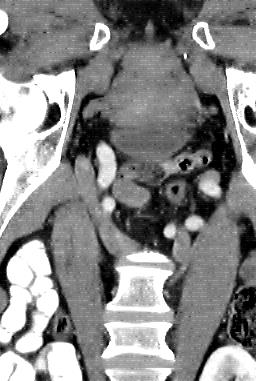

Due to the constraints of the imaging device and high cost in operation time, computer tomography (CT) scans are usually acquired with low intra-slice resolution. Improving the intra-slice resolution is beneficial to the disease diagnosis for both human experts and computer-aided systems. To this end, this paper builds a novel medical slice synthesis to increase the between-slice resolution. Considering that the ground-truth intermediate medical slices are always absent in clinical practice, we introduce the incremental cross-view mutual distillation strategy to accomplish this task in the self-supervised learning manner. Specifically, we model this problem from three different views: slice-wise interpolation from axial view and pixel-wise interpolation from coronal and sagittal views. Under this circumstance, the models learned from different views can distill valuable knowledge to guide the learning processes of each other. We can repeat this process to make the models synthesize intermediate slice data with increasing inter-slice resolution. To demonstrate the effectiveness of the proposed approach, we conduct comprehensive experiments on a large-scale CT dataset. Quantitative and qualitative comparison results show that our method outperforms state-of-the-art algorithms by clear margins.